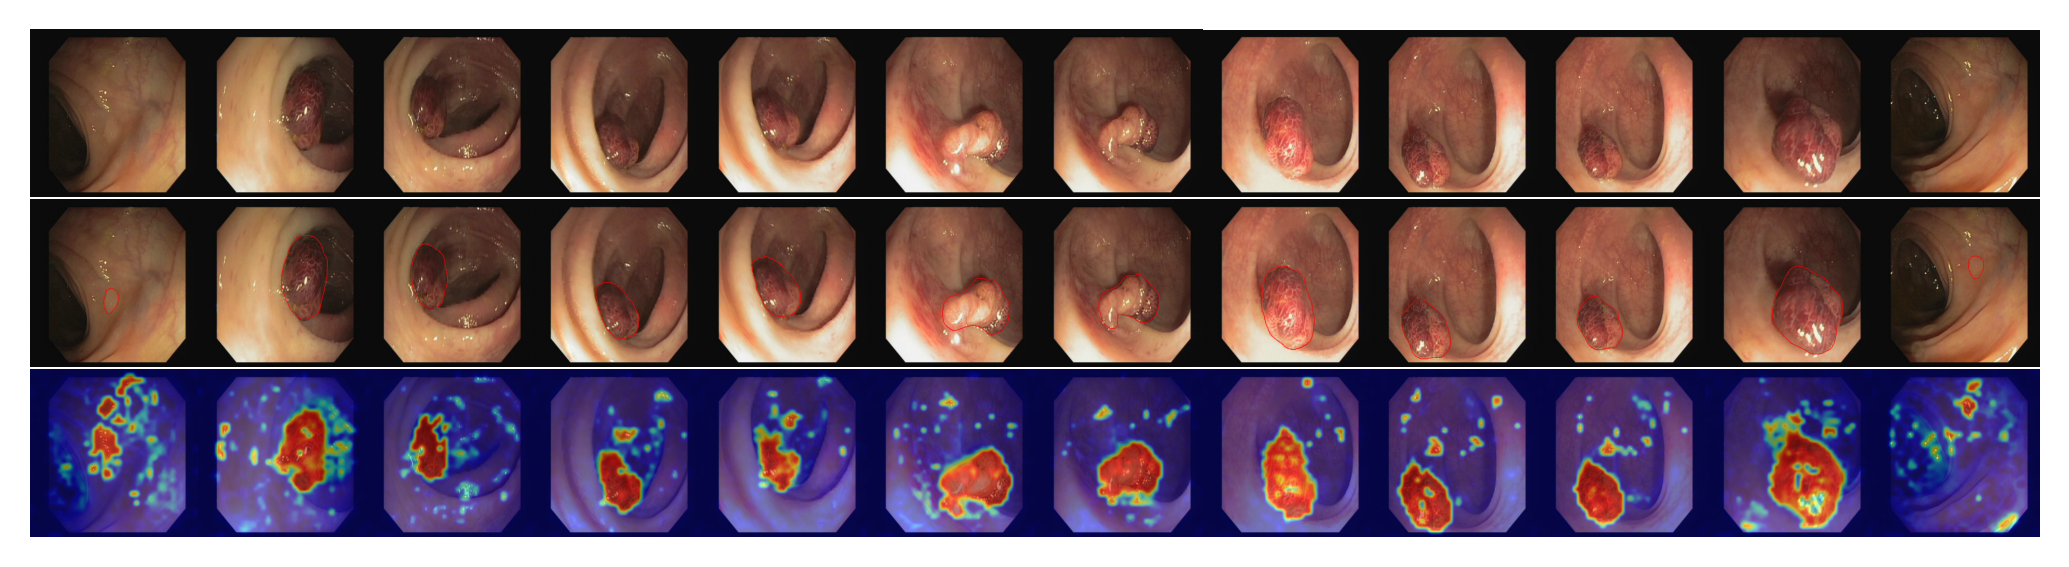

To evaluate the generalization ability of our model, we further examine the ZSAD performance of AnomalyCLIP on 10 medical image datasets of different organs across different imaging devices. Table 2 shows the results, where learning-based methods, including AnomalyCLIP, VAND and CoOp, are all tuned using MVTec AD data. It is remarkable that methods like AnomalyCLIP and VAND obtain promising ZSAD performance on various medical image datasets, even though they are tuned using a defect detection dataset. Among all these methods, AnomalyCLIP is the best performer due to its strong generalization brought by object-agnostic prompt learning. As illustrated in Fig. 4, AnomalyCLIP can accurately detect various types of anomalies in diverse medical images, such as skin cancer regions in photography images, colon polyps in endoscopy images, thyroid nodules in ultrasound images, and brain tumors in MRI images, having substantially better performance in locating the abnormal lesion/tumor regions than the other two methods WinCLIP and VAND. This again demonstrates the superior ZSAD performance of AnomalyCLIP in datasets of highly diverse object semantics from medical imaging domains.

Refer to caption

Figure 4: Segmentation visualization.

Anomaly score map for different datasets.

In addition to the similarity score for anomaly classification, we also visualize the anomaly score maps to present the strong anomaly segmentation ability of AnomalyCLIP. Specifically, we visualize the industrial object class: hazelnut, pill, and screw from MVTec AD; candle, chewinggum, capsule, cashew, pcb, and pip fryum from Visa; bracket, metal plate, and tube from MPDD. We also visualize the industrial texture: grid, leather, carpet, tile, wood, and zipper. In addition, we visualize the segmentation in medical domain across photography, endoscopy, and radiology images: skin cancer detection from ISIC; thyroid nodule detection from TN3K; colon polyp detection from Kvasir; brain tumor detection from Br35H.

Figure 34: Anomaly score maps for the data subset thyroid. The first row represents the input, and we circle the anomaly regions in the second row. The last row presents the segmentation results from AnomalyCLIP.